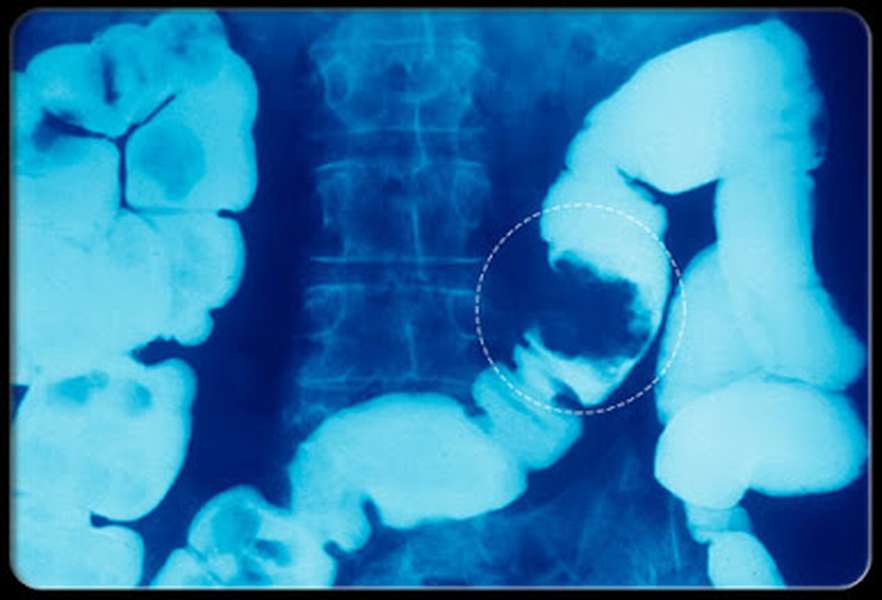

Click vào ảnh để xem 3 hình ảnh minh họa